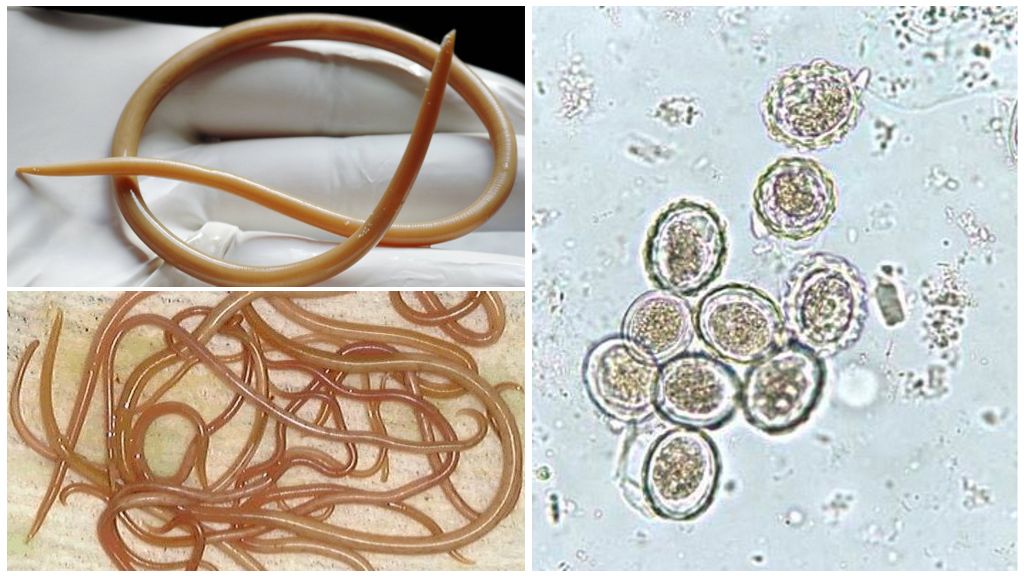

Фотографии нематод, цестод и трематод в природе

Раздел: Другие животные